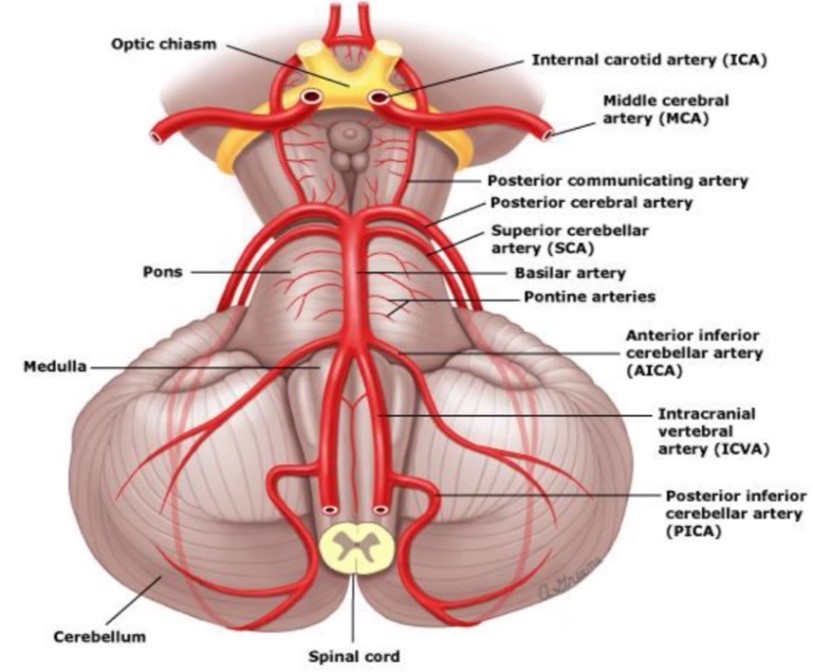

Stroke i vertebrobasilarisområdet

- Yrsel

- Nystagmus (ofta grovvågig med snabb fas mot skadesidan)

- Hemiataxi (ipsilateral)

- Dysfagi, heshet

- Dysartri

- Känsdelnedsättning ipsilateralt i ansikte och motsatt sida på kroppen

När ses dessa symptom och vad kallas det för?

Stroke i PICA-artären (även a. vertebralis)

Wallenbergs syndrom